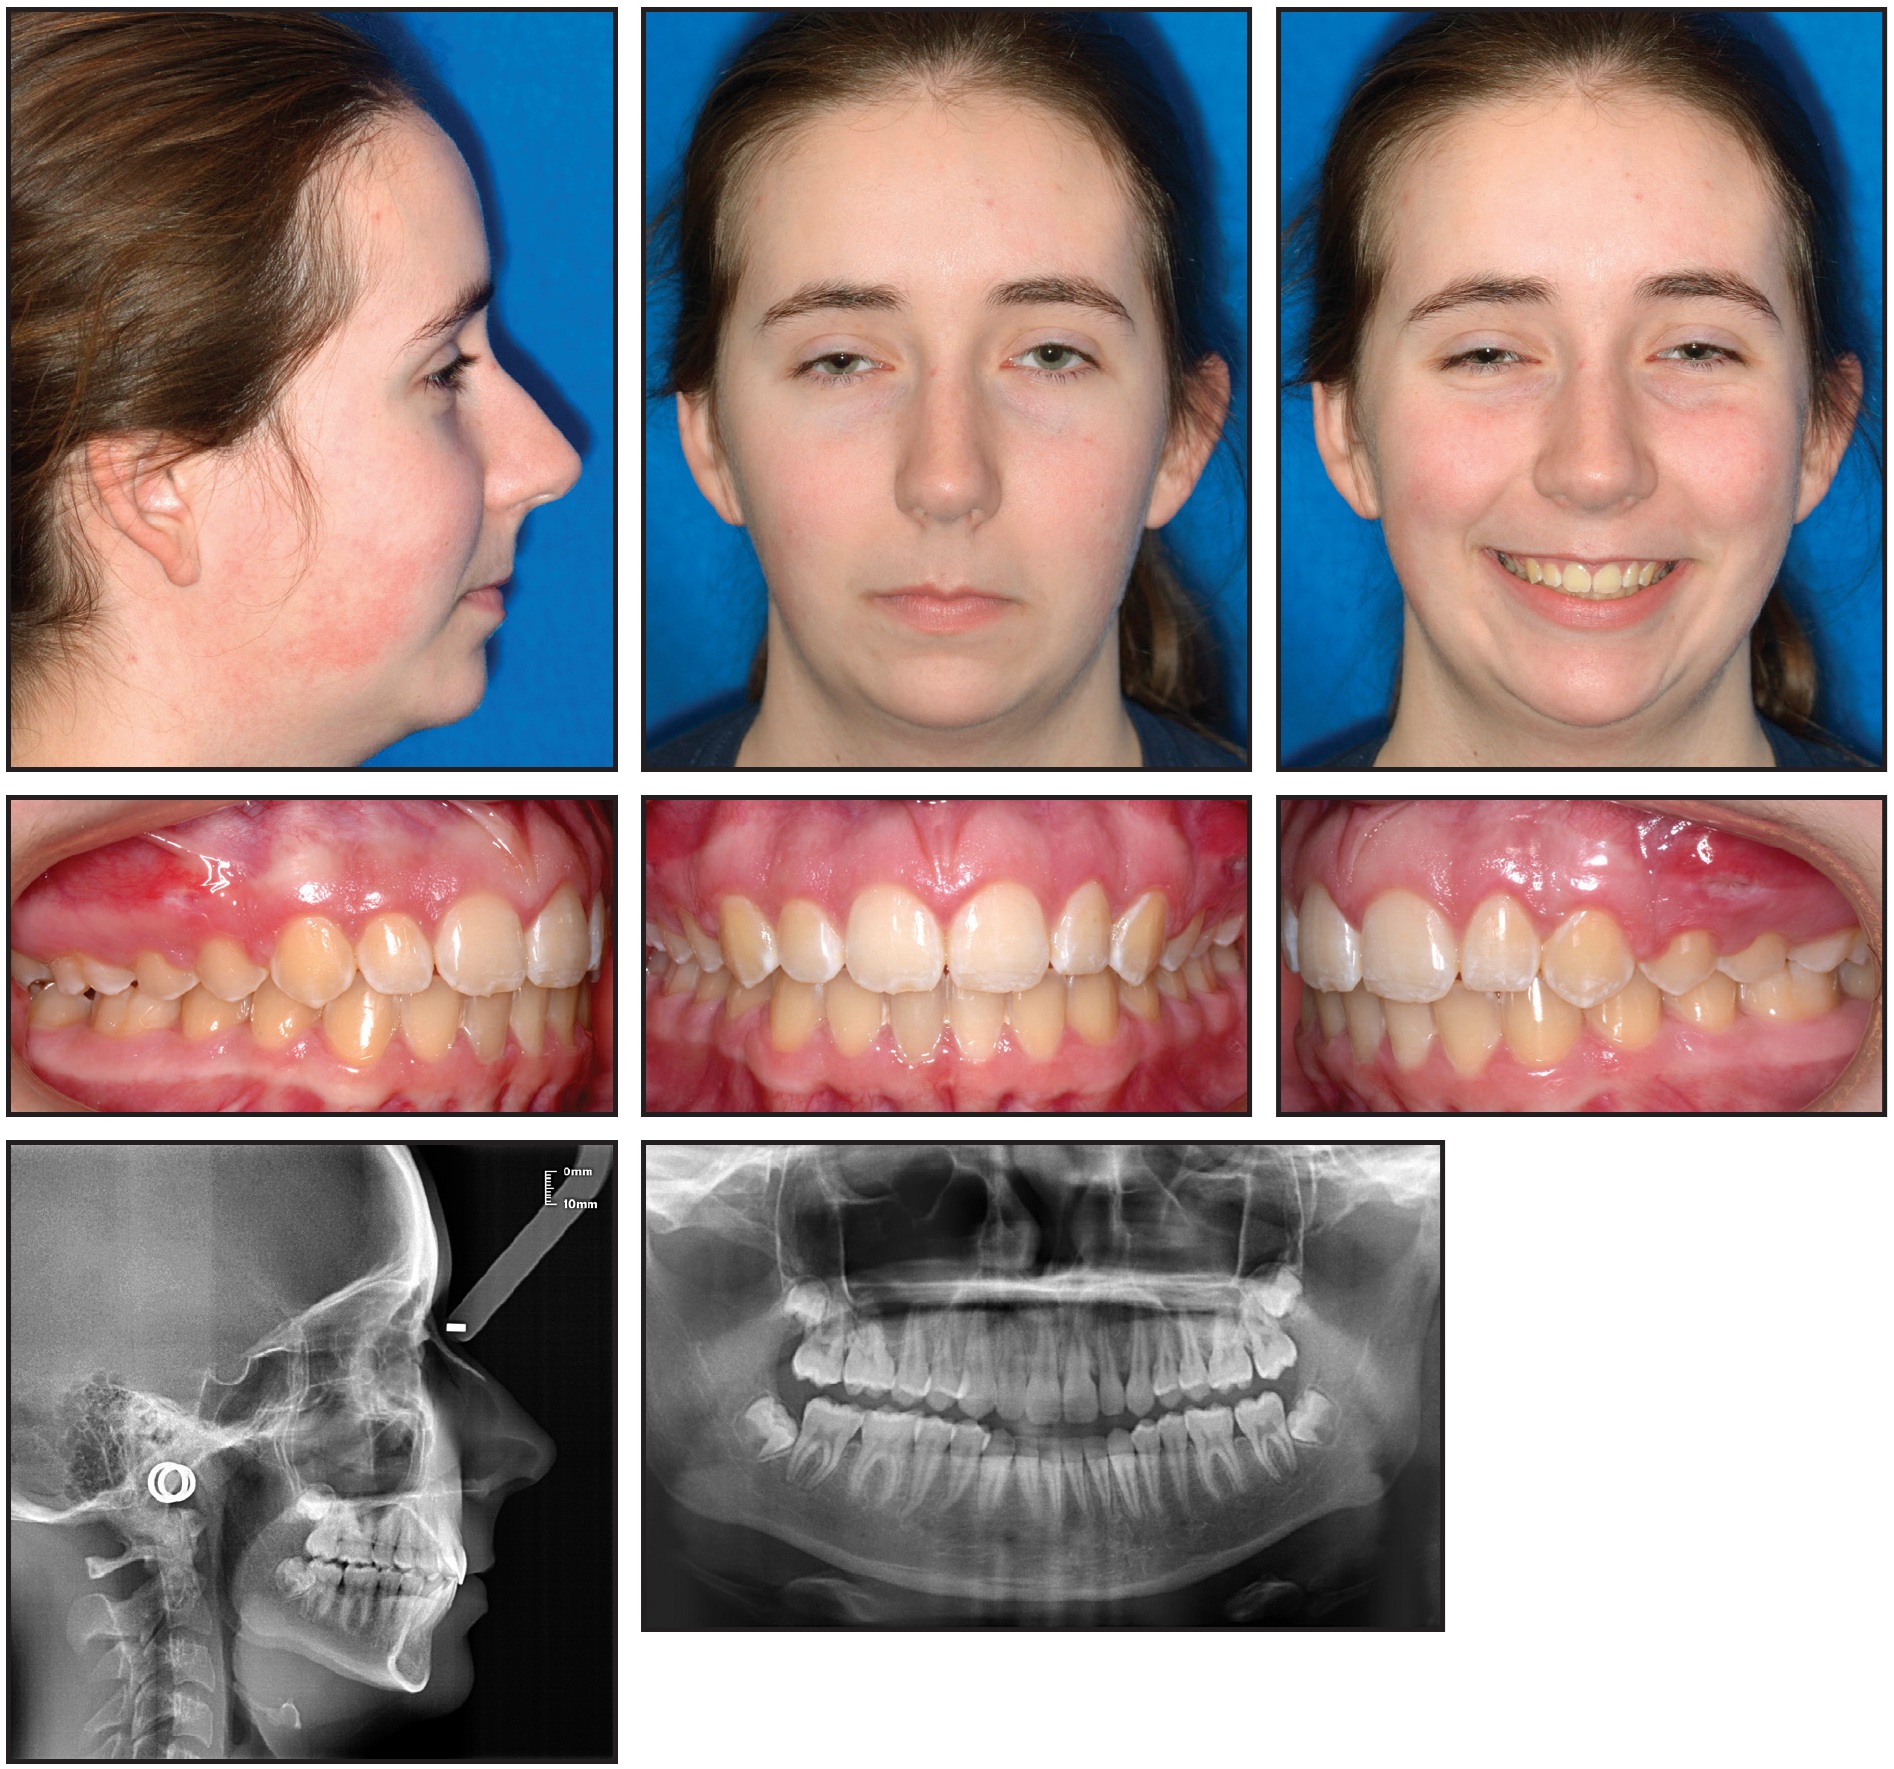

The patient's use of vibration during that period was recorded as an average of 29 times per month. Treatment was completed in 16 months with 15 visits (Fig. 6).

Fig. 6 Patient after 16 months of treatment with 15 visits.